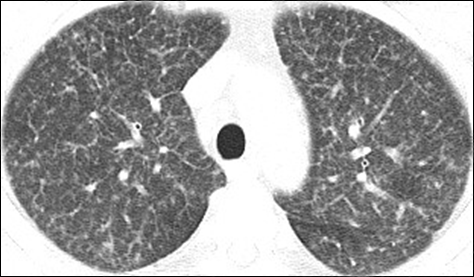

影像学资料:

2017年3月

2017年7月

2018年2月

2018年3月